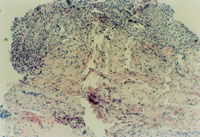

3-17 取燒傷皮膚組織進(jìn)行組織切片,診斷為全厚皮壞死,部分脂肪層組織壞死

3-23 對(duì)其“皮點(diǎn)”進(jìn)行組織學(xué)檢查,該組織為從皮下組織中再生出的微血管、膠原組織、表皮細(xì)胞組織組成的再生皮膚組織團(tuán)